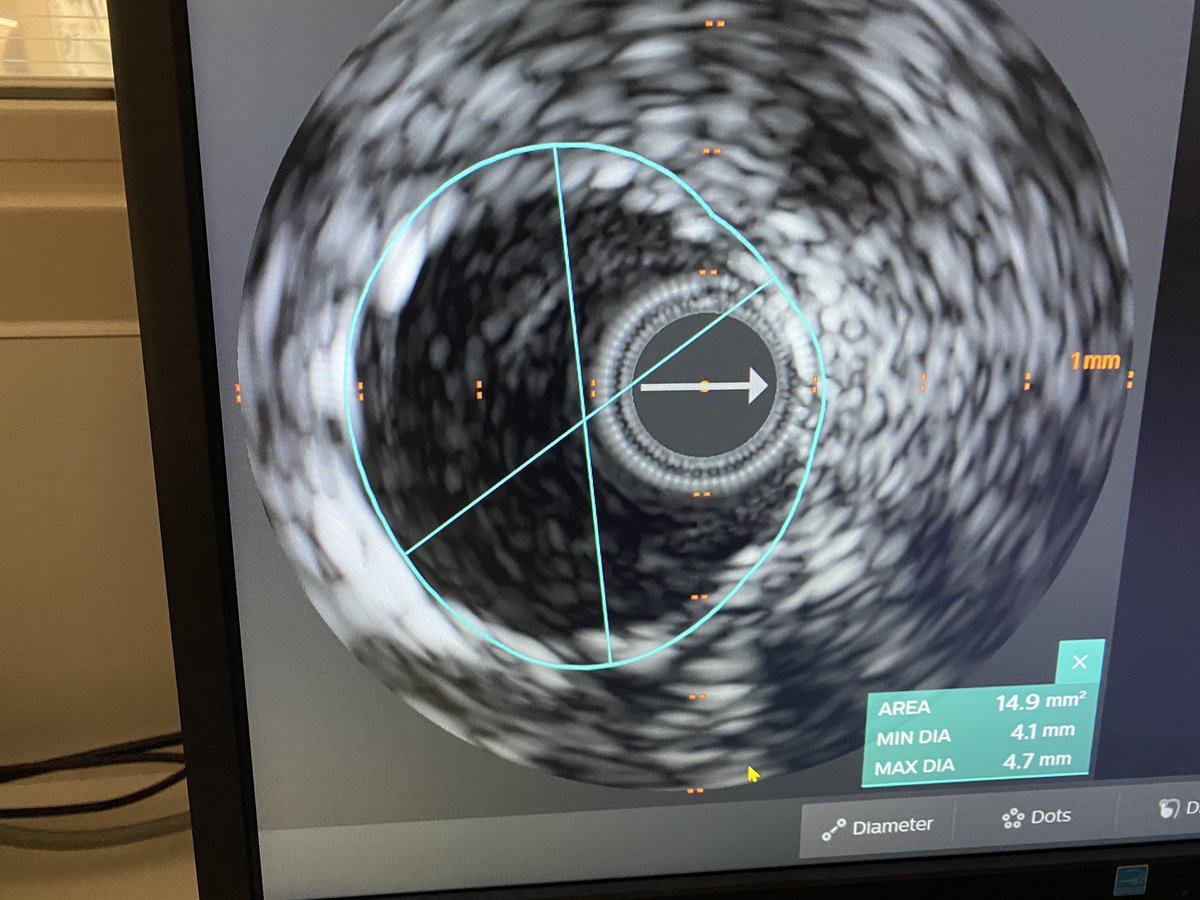

IVUS showed prior LAD 2.75mm stent in 4.25 vessel and 4.5mm in more Prox segment.

Dropped new stent 4.5mm and postdilated old stent to 4.25mm. Post IVUS with excellent expansion and no more malapposition. Looks grossly oversized on post angio.